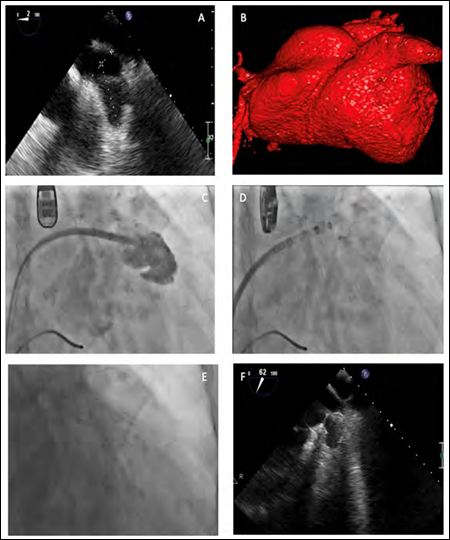

A 78-year-old active woman had undergone orthotopic heart transplantation in 2008. She developed paroxysmal Atrial Fibrillation (AF) six years after transplantation and was started on oral anticoagulation. Two years later, oral anticoagulant therapy was stopped due to repeated severe arm hematomas, despite her high thromboembolic risk. Following a multidisciplinary team evaluation, LAA occlusion was therefore indicated. Cardiac tomography assessment revealed a chicken wing LAA (Figure 1, Panel B), measurements were 40*29mm.

LAA orifice diameter was 30mm and the depth was 40mm on Transesophageal Echocardiography (TEE) (Figure 1, Panel A). Despite of anatomical changes post biatrial anastomosis OHT, the standard WATCHMAN TEE implantation views were adequate (Figure 1, Panel A). A BRK© transseptal needle with an accentuated 30°curve was used to puncture the interatrial septum. A 33mm plug was successfully delivered to the LAA on the first attempt (Figure 1, Panels D and E). The patient was discharged on Clopidogrel and Aspirin therapy.

Figure 1: A) Transesophageal Echocardiography (TEE) view of the Left Atrial Appendage (LAA) ostium maximum diameter (30mm). B) Tomography reconstruction of the LAA. C) LAA opacification. D and E) Fluoroscopic view of a 33mm Watchman device successful deployment. F) Good device position after deployment on TEE.

A TEE at 30 days demonstrated no thrombus and no residual flow in the LAA. Clopidogrel was discontinued after one month and the patient wasplaced on Aspirin in long term. After a 6 months follow-up the patient is free from bleeding and cardioembolic events.